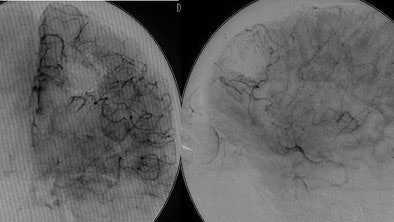

| Digital subtraction angiography shows arteriovenous malformation at presentation (top, below) and two weeks postembolization (bottom) with endovascular administration of ethylene vinyl alcohol copolymer embolization agent (Onyx, Micro Therapeutics, Irvine, CA). The patient had repetitive transient ischemia attacks due to cerebral steal from the AVM. Images courtesy of Dr. Michael Forsting. |

In another example, a patient with an AVM located in the speech center of the patient's brain was a "No-touch AVM" for the neurosurgeon if not the endovascular therapist, according to Forsting. "We know these are pretty dangerous," he said. "Nowadays we go in with a catheter and we can occlude them completely." Late-venous-phase CT three weeks later showed complete occlusion, and the patient suffered no neurologic deficit.

The risk of surgery is largely dependent on the size of the AVM, Forsting said. A large AVM brings a 50% risk, which is reduced tenfold for smaller AVMs.

"Endovascular therapy is mandatory in all patients with AVM, and you need to treat all patients with AVM," he said. A 2002 study by Simon et al examined the long-term outcomes of patients with intrinsic brain AVM. Over an average 10 years of follow-up, conservative management produced a 24.6% mortality rate, while active management reduced mortality and morbidity to 3.9% (p = 0.031), Forsting said (Stroke, December 2002, Vol. 33, pp. 2794).